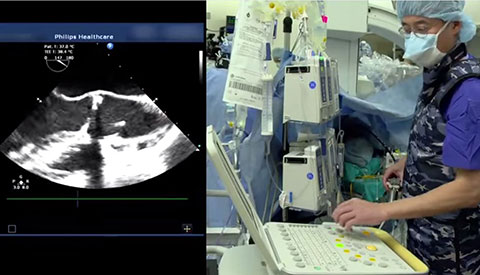

تم تشخيص أحد المرضى لديك بتضيّق في الصمام الأورطي المصحوب بأعراض. يبلغ عمر المريضة 85 عامًا وهي تعاني من السكري وارتفاع ضغط الدم. أنت تدرك خطورة وضعها الصحي ما يجعلها غير مناسبة لجراحة القلب ولكن يسمح لها بأن تكون مرشحة لاستبدال الصمام الأورطي باستخدام القسطرة (TAVR). في يومنا هذا، تمنح حلول التصوير المبتكرة والأجهزة التي تعمل عن طريق الجلد الأمل لبعض المرضى الذين لا تتوفر لهم حتى الآن أي خيارات علاجية أخرى.